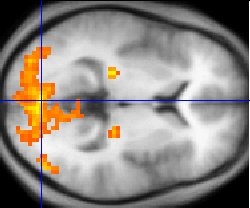

To discern what was happening to the brain, itself, Li's team used

functional magnetic resonance imaging (fMRI) on a dozen human subjects as they processed neutral odors in an anxious state. Li's team found that the separate brain areas known to process smell and emotion became intertwined under conditions of anxiety, the brain working from a unified network of these systems. It appears that the emotional state becomes part of olfactory processing when a person becomes anxious.[2]

Figure captionFunctional magnetic resonance image, not from the University of Wisconsin study, showing brain areas involved with processing moving images.

(

Via Wikimedia Commons.)